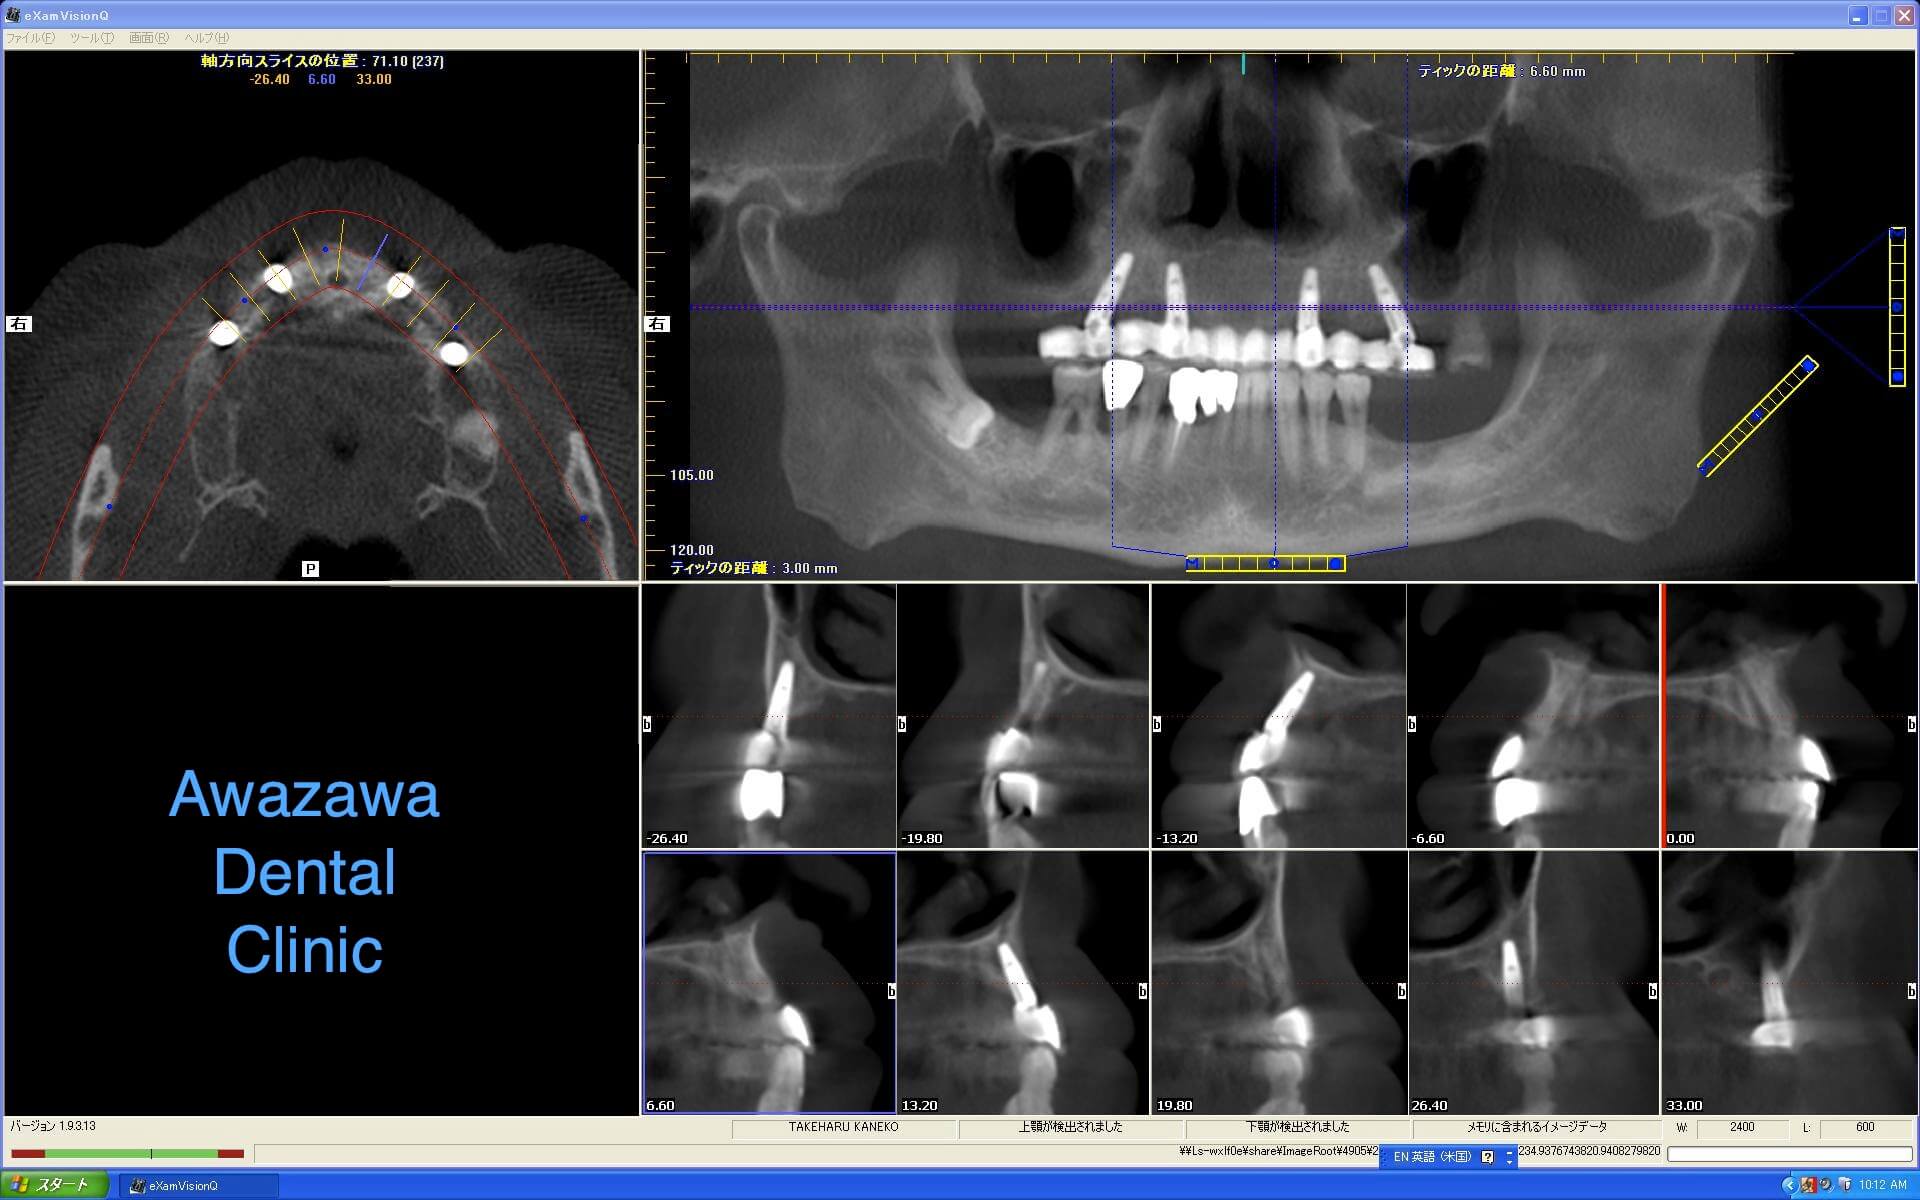

咬合崩壊状態の症例です。すべてインプラントによる再建を行いました。(治療後の写真は治療終了3年経過後の状態です。)

*上部構造装着3年経過後のCT画像です。シミュレーションによるインプラントの適正な配置が再現されているのが確認できます。